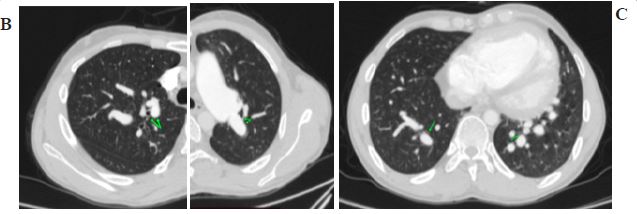

Figure 1: (B) Lung window chest computed tomography (CT) axial section images demonstrating the diameters of apical segmental bronchi of RUL (A of RUL) and apicoposterior segmental bronchi of LUL (AP of LUL) with their adjacent segmental bronchial artery to calculate segmental pulmonary artery to bronchus ratio which came out to be 0.8 and 1.1 respectively. (C) Lung window chest CT axial section image demonstrating the diameters of posterobasal segmental bronchi of right and left lower lobes (PB of RLL and PB of LLL respectively) with their adjacent segmental bronchial artery to calculate segmental pulmonary artery to bronchus ratio (1.1 and 1 respectively).